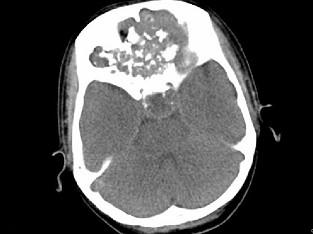

男,26岁,进行性鼻腔阻塞、流涕来院就诊,近两年持续性头痛、头晕,如图所示筛窦区占位灶应诊断为 ( )